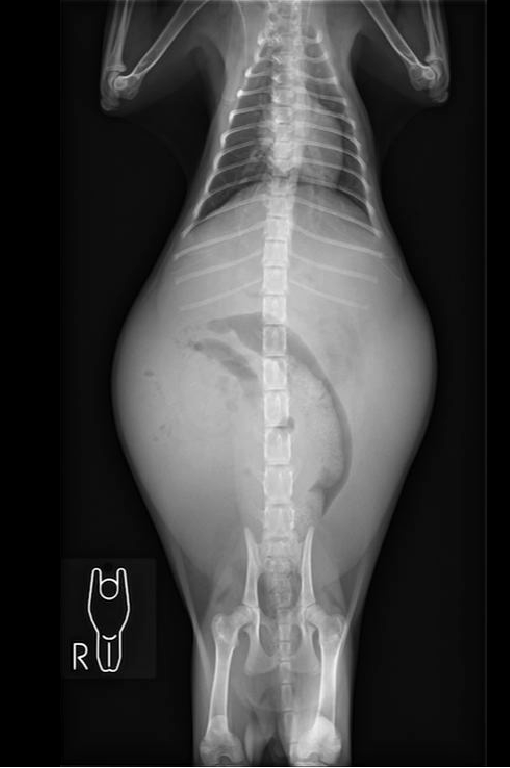

[発症前(10月時点)] ➡ [発症後]

腹水が溜まり、お腹が横に広がっているのがわかると思います。